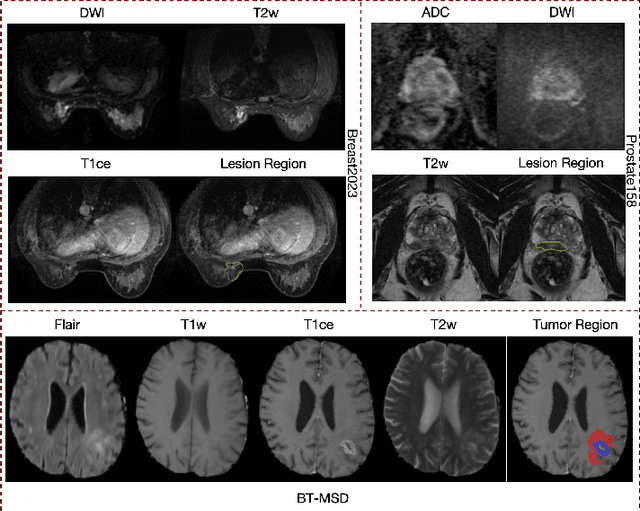

Abstract:Magnetic resonance imaging (MRI) is indispensable for diagnosing and planning treatment in various medical conditions due to its ability to produce multi-series images that reveal different tissue characteristics. However, integrating these diverse series to form a coherent analysis presents significant challenges, such as differing spatial resolutions and contrast patterns meanwhile requiring extensive annotated data, which is scarce in clinical practice. Due to these issues, we introduce a novel Cross-Series Masking (CSM) Strategy for effectively learning MRI representation in a self-supervised manner. Specifically, CSM commences by randomly sampling a subset of regions and series, which are then strategically masked. In the training process, the cross-series representation is learned by utilizing the unmasked data to reconstruct the masked portions. This process not only integrates information across different series but also facilitates the ability to model both intra-series and inter-series correlations and complementarities. With the learned representation, the downstream tasks like segmentation and classification are also enhanced. Taking brain tissue segmentation, breast tumor benign/malignant classification, and prostate cancer diagnosis as examples, our method achieves state-of-the-art performance on both public and in-house datasets.